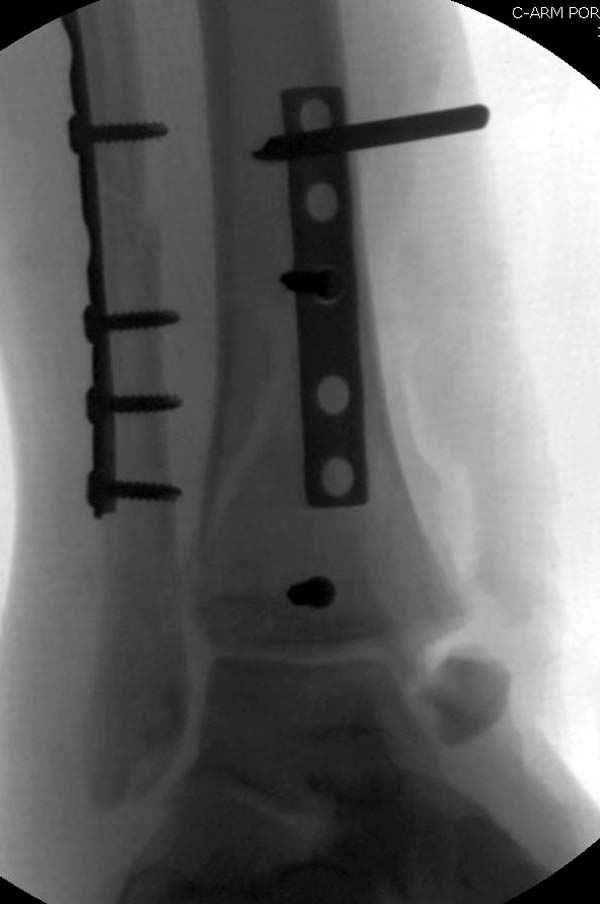

Из заднего доступа остеотомия тонким остеотомом и коррекции на ЭОПе.

Без применения сложной конструкции, а обычными параллельными шурупами. Шурупы в 3.5 мм и дополнительно фиксация крючковидной пластиной, сделанной из 3.5 mm semitubular пластиной, Butress или аntiglade фиксация.

Здесь алгоритм фиксации свежего перелома и преоперационный план для обсуждаемого случая.